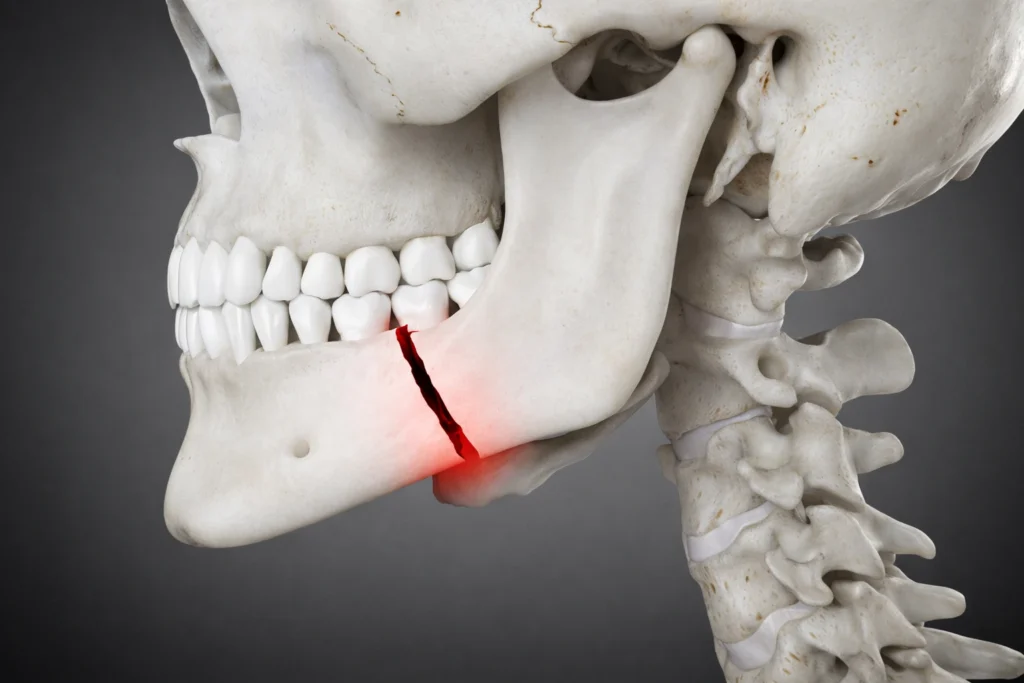

TMJ and Orofacial Pain

Chronic pain is one of the most debilitating conditions a person may suffer from, and orofacial pain is one of these conditions. It can range from toothache to Temporomandibular Joint (TMJ) pain to Neuralgia pain. So, it may often get confused with another type of chronic pain, such as migraine, sinusitis, temporal headache, etc. Therefore, correct diagnosis is critical in such conditions since wrong diagnoses can lead to unwanted treatments.

Jaw Deformities and Facial Aesthetic Surgeries

Developing abnormal jaw growth can cause protruding chins, gummy smiles, inability to chew, tongue thrusting, sleep apnoea, and lisping. Therefore, camouflage treatment can control and manage the deformity without surgery with the right intervention. If the deformity is too obvious and extensive, it’s better to have a maxillofacial surgeon and orthodontist work together.

Facial Trauma Care

Maxillofacial trauma may vary from simple tooth loss during a fall to pan facial injuries and fractures due to road traffic accidents. Therefore, a team of doctors at Share A Smile and associated hospitals provides a thorough multi-specialty intervention and a wholesome approach, which is needed for their treatment. Additionally, We can help you with fracture fixation, fixed replacement of lost teeth, minimal scar suturing, and scar revision.